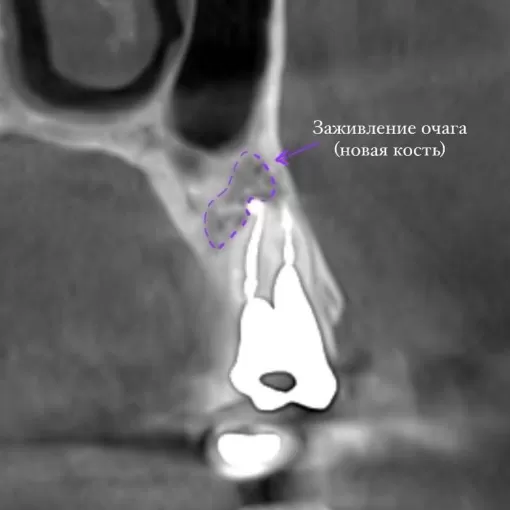

Клинический случай лечения "кисты" зуба 4.7

Стоматолог-терапевт Петрусенко О.А.

Пациент обратился с целью имплантации в области отсутствующего зуба 4.6. Однако после КЛКТ (3Д) исследования был обнаружен воспалительный процесс (киста) в области соседнего зуба 4.7 (рис. 1).